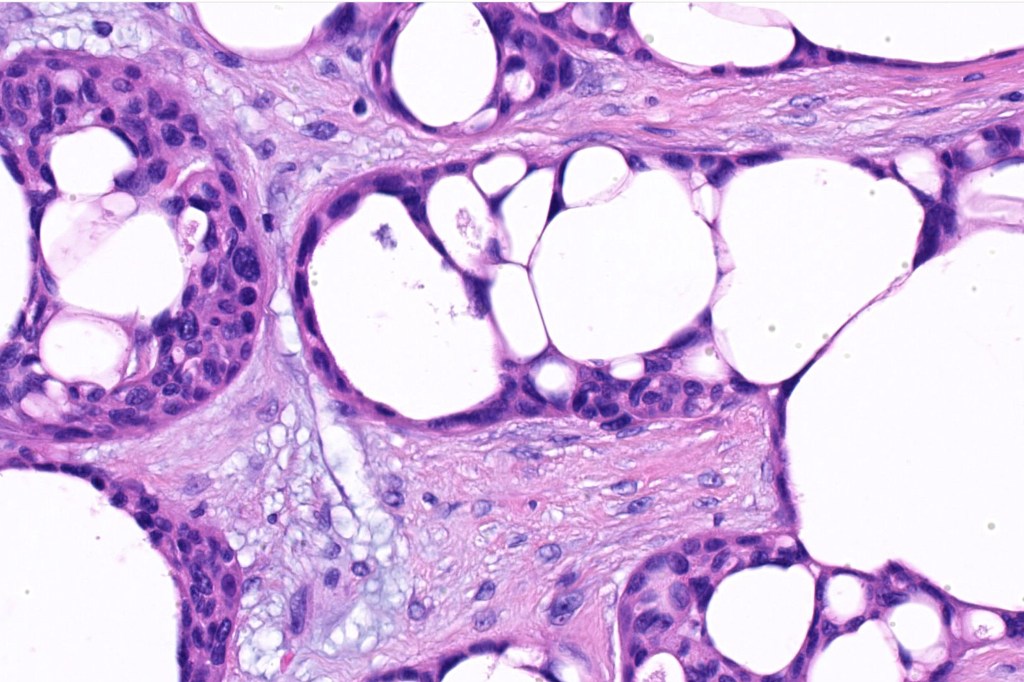

Histological features

•Generally circumscribed nodules/cysts

•Interconnecting epithelial strands giving rise to the cribriform growth pattern

•Ductal differentiation

•Hyperchromatic nuclei with variable pleomorphism

•Mitoses sparse or absent

•Focal decapitation secretion and presence of more typical apocrine carcinoma-like nests